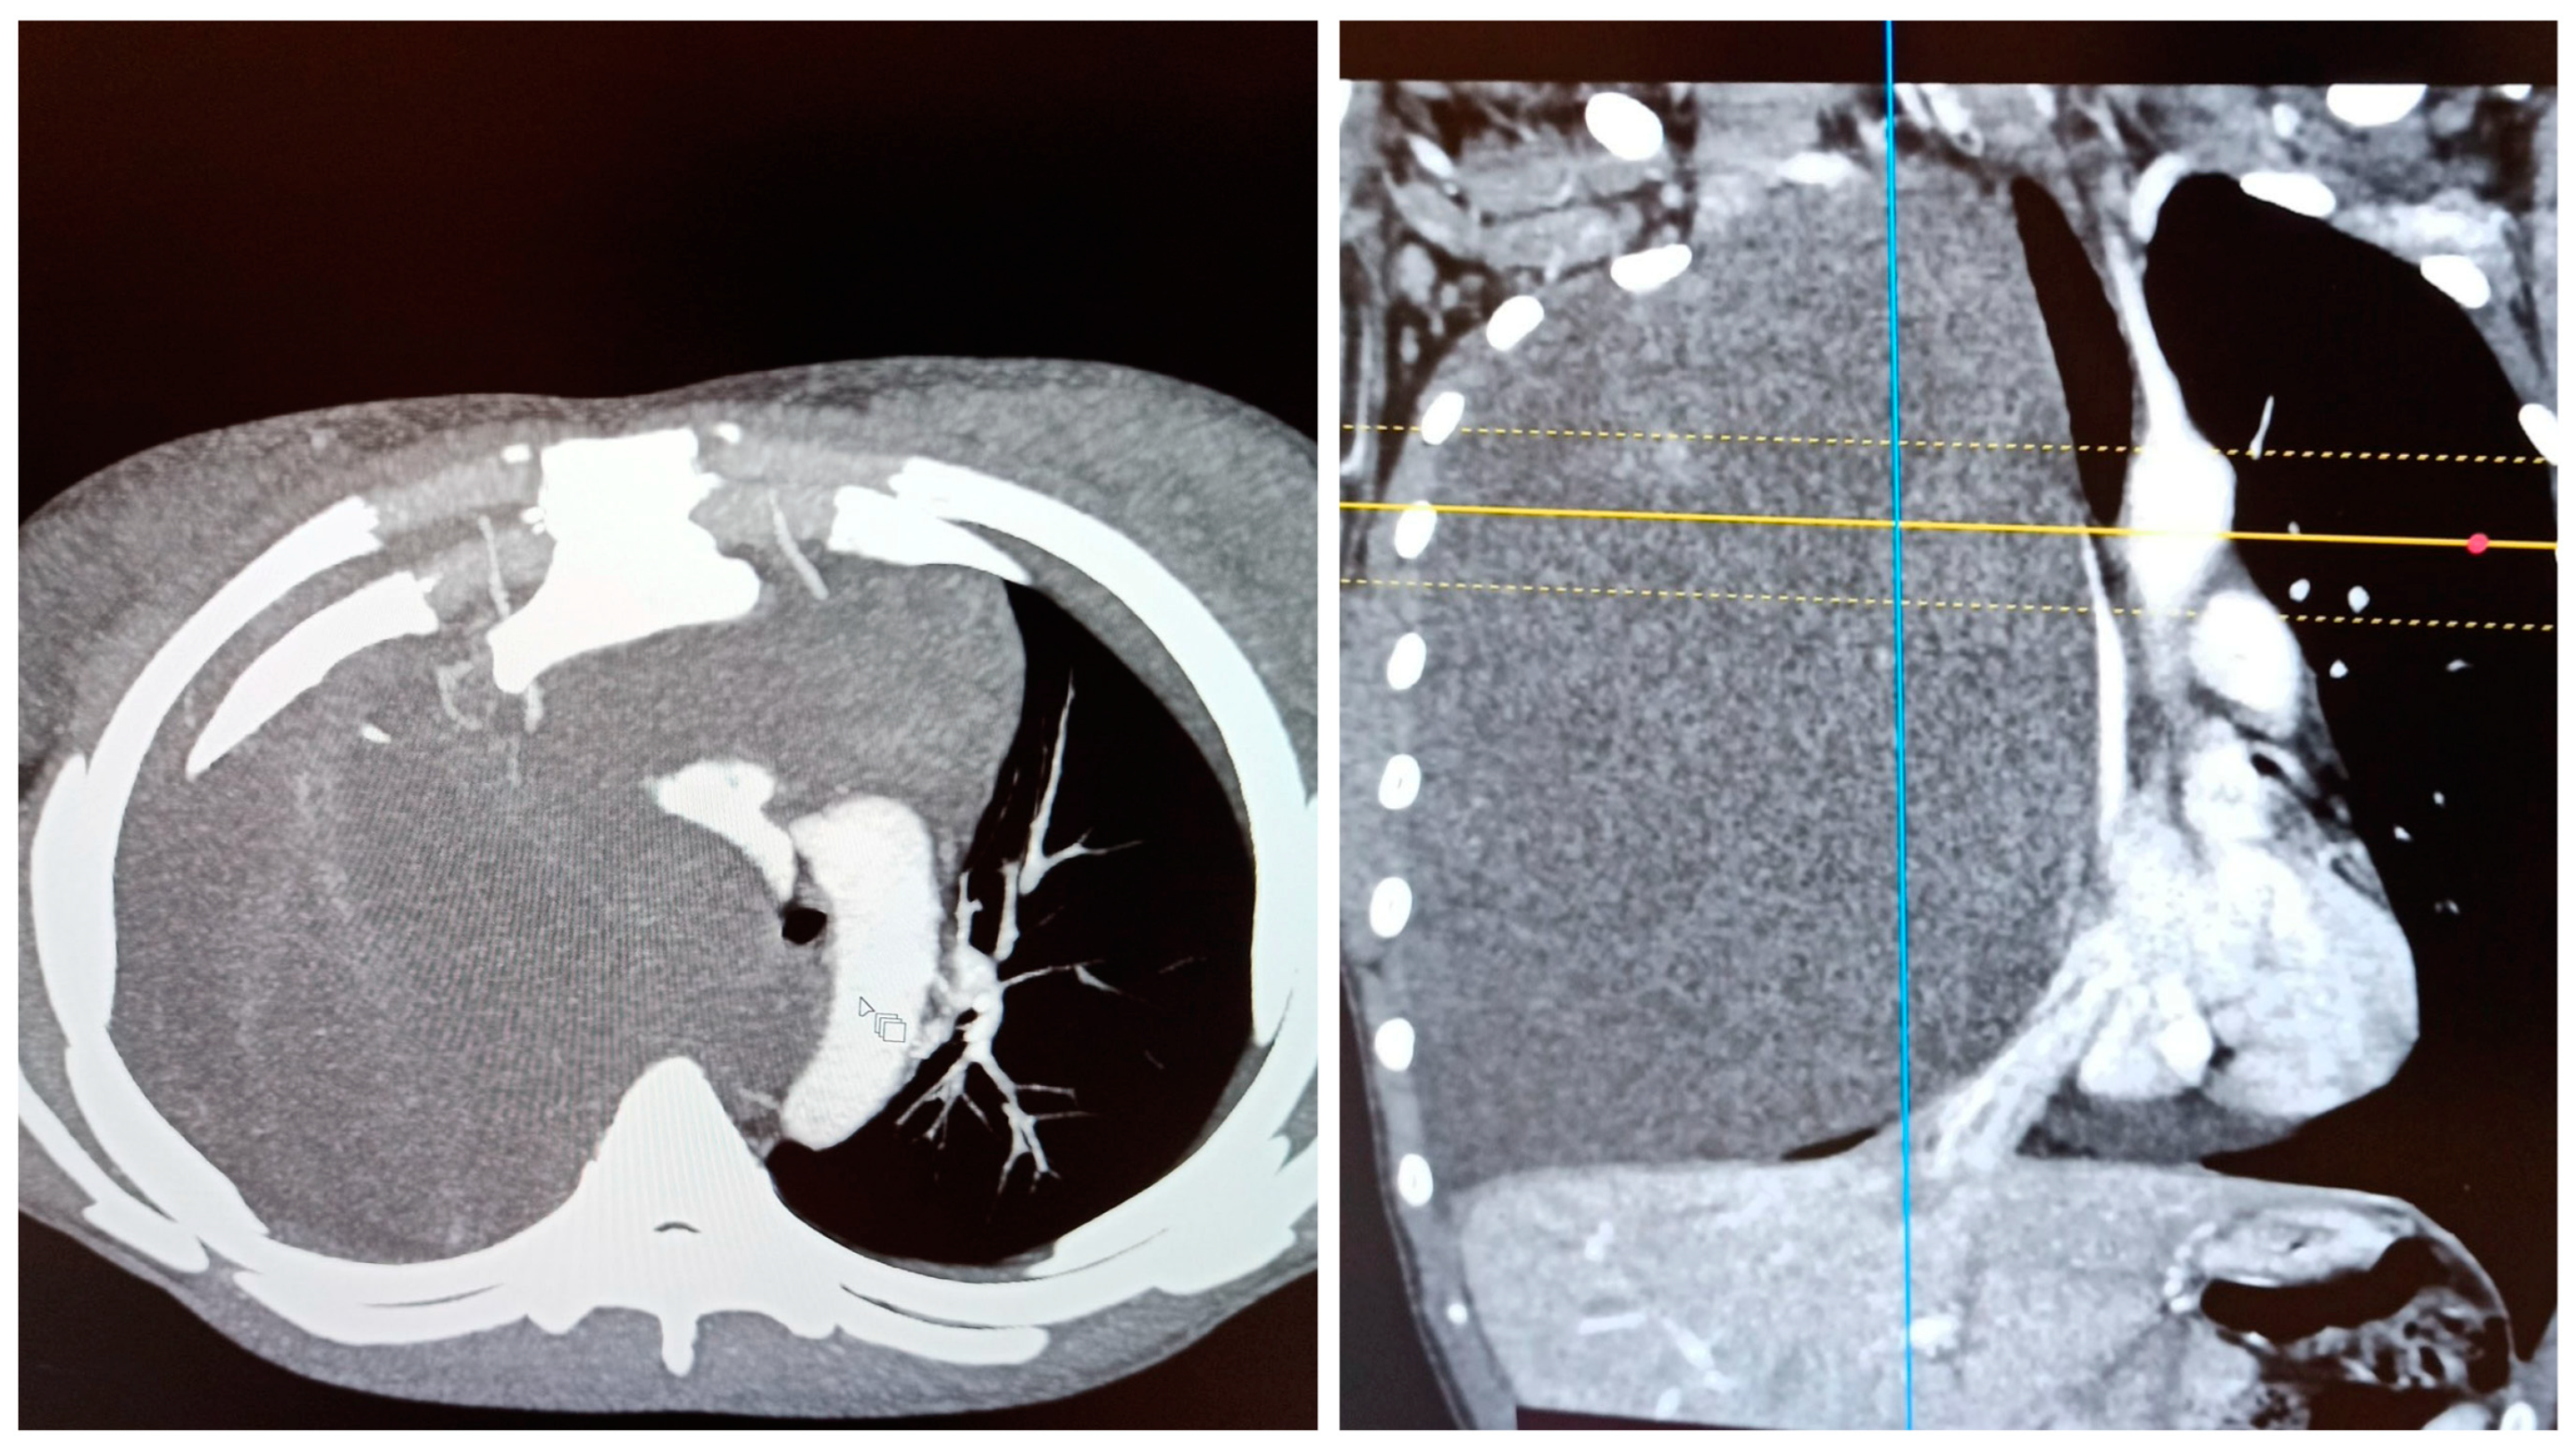

Large Intrathoracic Desmoid Tumor and Re-Expansion Pulmonary Edema: Case Report and Review of the Literature

2. Case Report